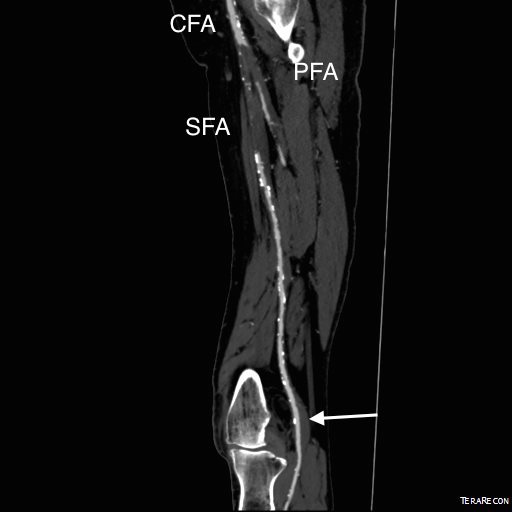

The patient presented with complaints of leg and foot pain with sitting and short distance calf claudication, being unable to walk more than 100 feet. This is unusual because sitting usually relieves ischemic rest pain. He is in late middle age and developed claudication a year prior to presentation that was treated with stent grafting of his superficial femoral artery from its origin to Hunter’s canal at his local hospital. This relieved his claudication only briefly, but when the pain recurred a few months after treatment, it was far worse than what he had originally. Now, when he sat at his desk, his foot would go numb very quickly and he would have to lie down to relieve his pain.

On examination, the patient was moderately obese with overhanging belly. He had a palpable right femoral pulse, but nothing below was palpable. He had multiphasic signals in the dorsalis pedis and posterior tibial arteries. The left leg had a normal arterial exam. Pulse volume recording and segmental pressures were measured:

These are taken with the patient lying down which was the position that relieved his pain, and the PVR’s show some diminishment of inflow. It would be easy at this point to declare the patient’s pain to be due to neuropathy or spinal stenosis, but because of his inability to walk more than a hundred feet and because of his severe pain with sitting, I went ahead and obtained a CTA.

The CTA showed he had an occluded superficial femoral artery (SFA) with patent profunda femoral artery (PFA) with reconstitution of an above knee popliteal artery with multivessel runoff. The 3DVR image showed his inguinal crease to be right over the femoral bifurcation which is not an unsual finding, but his stent graft was partially occluding his profunda femoral artery.

I decided to take him to the operating room to relieve his PFA of this obstruction. My plan was to remove the stent graft at the origin of the SFA and at the same time, remove the plaque and occluded stent graft from his SFA to restore it to patency.

In the OR, on exposing his SFA, I discovered that because of his overhanging belly, his inguinal ligament had sagged and was compressing his femoral bifurcation.

This explained his presentation. The stent graft really had no chance as when he sat, the belly and ligament compressed it at the origin, and because it partially occluded the origin of the PFA, sitting probably pinched off flow completely. The 3dVR image shows the mid segment of PFA to have little contrast density -this is not because of thrombus, but because of the obstruction, the PFA was getting collateral flow from the hypogastric artery.